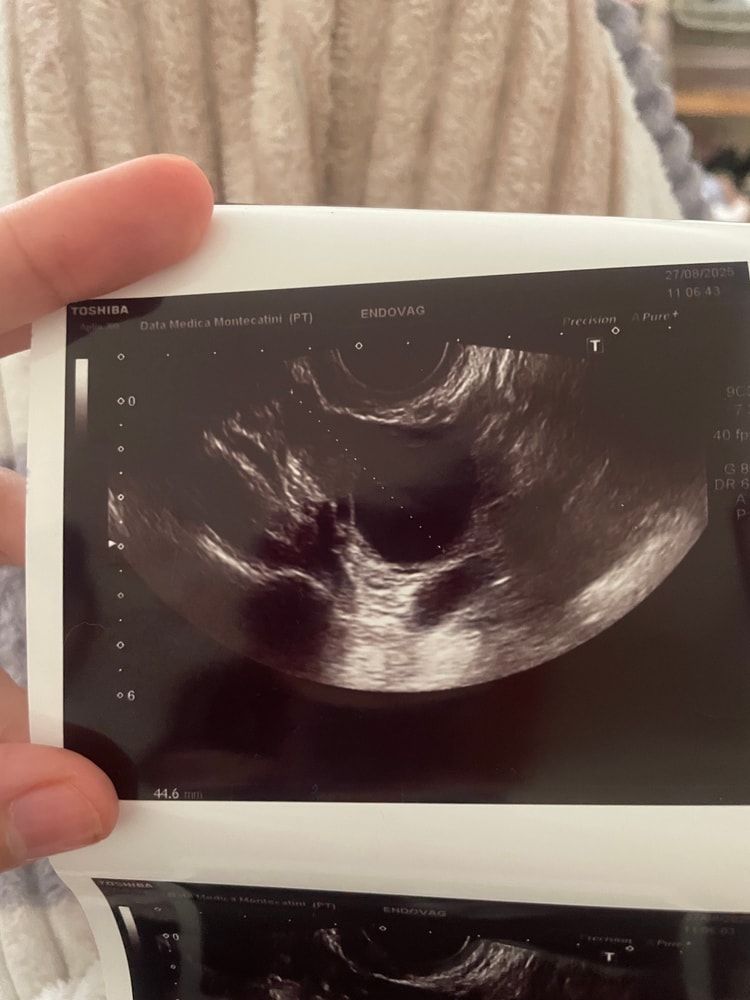

Девочки, подскажите, пожалуйста. Была на УЗИ и мне сказал врач что и на правом и налево яичники есть кисты ( 28*24 мм и 28*36 ) . Спросив какого они типа - он сказал что нужно наблюдать , пока Это не страшно , могут сами пройти . Вопрос такой , с кистами забеременеть нереально ? Они влияют на О ??? Хоть по графику бт она бывает, но …. капец ,аж 2 кисты 😭🤷🏻♀️

p.s. Сегодня поднялась бт , разболелась голова и появились выделения как обычно после О . Значит она случилась , и среди этих «кист» как минимум 1 доминантный фоликул был . Посмотрим дальше.